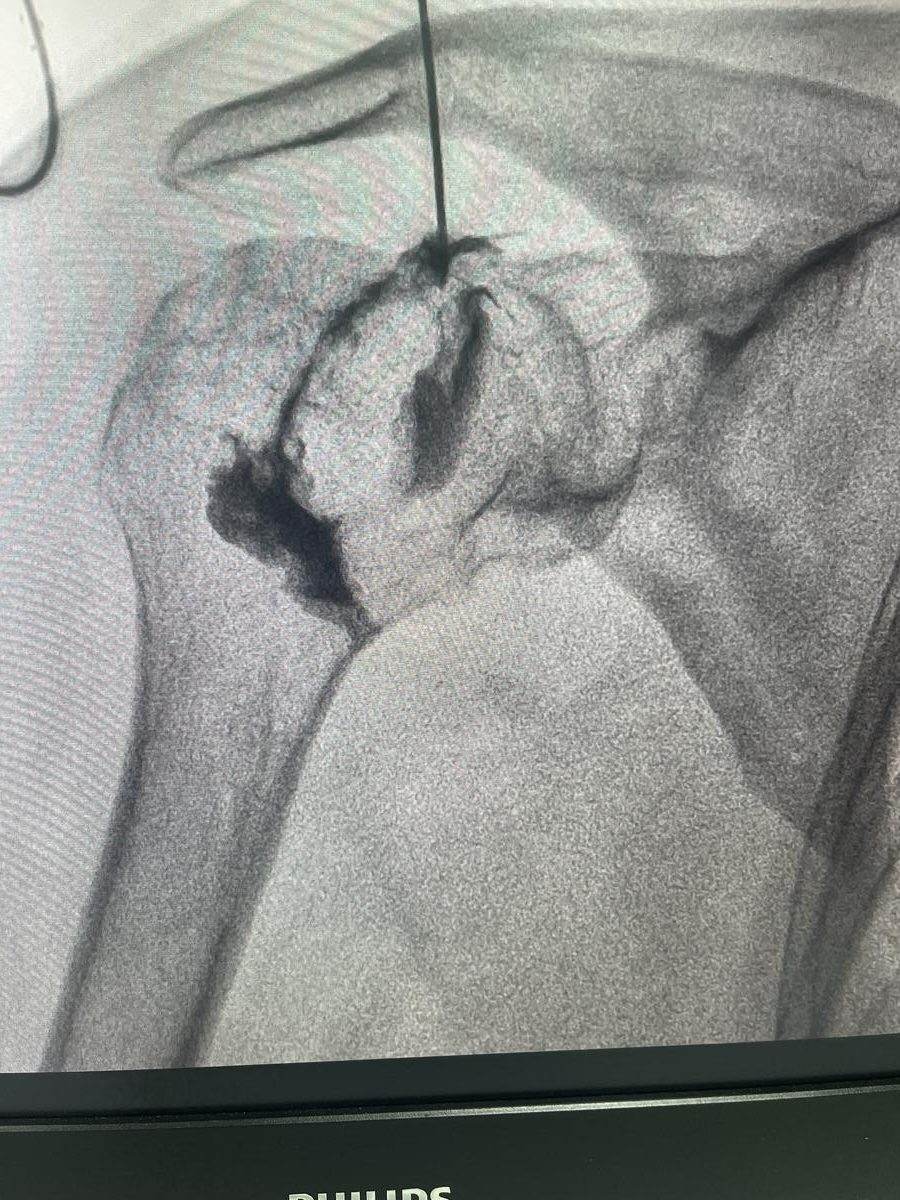

Hydrodilatation, a procedure that uses guided injection of fluid to expand and stretch the joint capsule, can significantly accelerate recovery and reduce pain when performed at the right stage of the condition.

• Hydrodilatation for frozen shoulder, guided capsule expansion to restore movement

What is hydrodilatation and how does it help frozen shoulder?

Hydrodilatation is an image-guided procedure where a mixture of saline, local anaesthetic, and corticosteroid is injected into the shoulder joint under pressure. This expands the contracted capsule, reduces inflammation, and helps restore range of motion. It is most effective during the freezing and frozen stages of adhesive capsulitis.